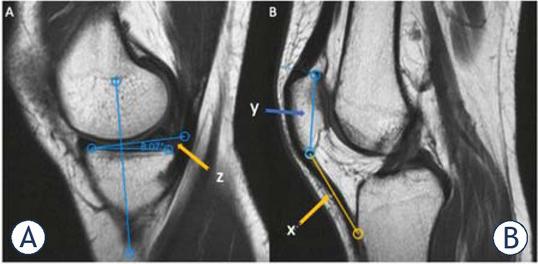

(A, B) Sagittal T1-Weighted MR images illustrating medial tibial slope and Insall-Salvati index. (Medial tibial slope, z: the angle formed between the line running along the tibial slope of the medial tibial condyle and the perpendicular line to the tibial axis; Insall-Salvati index: the ratio of x to y; x, the length of patellar tendon and y, the greatest diagonal length of patella)